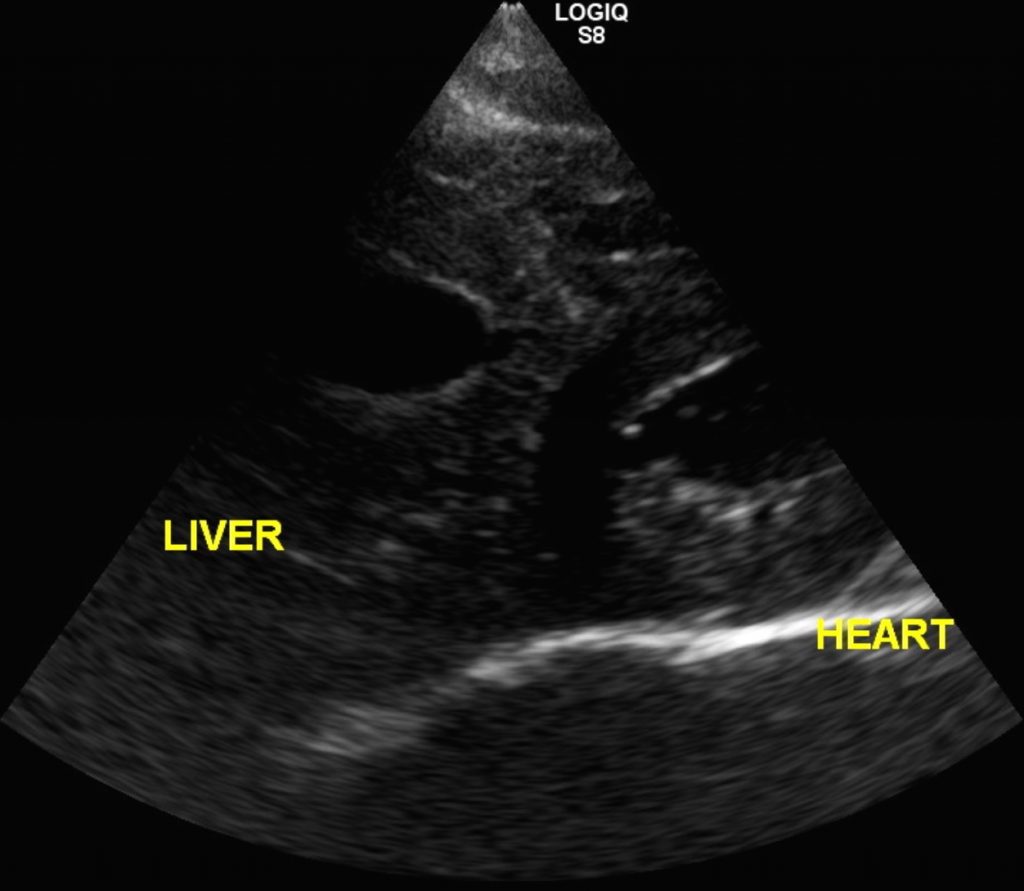

循環器疾患 症例紹介 診療案内 三重動物医療センター なるかわ動物病院

心膜横隔膜ヘルニアの外科手術と保存療法 それぞれの予後とは Vets Tech

猫の心膜横隔膜ヘルニア 猫9ヶ月齢の1例 手術で完治しました 大和市の花岡動物病院ブログ